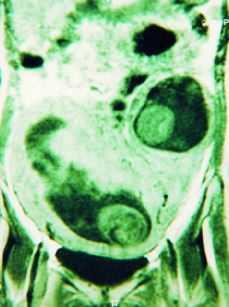

En el curso de su cuarta gestación, en la ecografía realizada a las 18 semanas de amenorrea se estableció el diagnóstico de sospecha de gestación gemelar heterotópica, con un feto en localización intrauterina y otro en un posible cuerno uterino rudimentario (Fig. 1). Este diagnóstico se confirmó mediante RMN, que además aportó el dato de la inexistencia de comunicación entre ambas cavidades (Fig. 2).

Figura 2. RMN realizada a las 18 semanas. Se confirma el diagnóstico de embarazo gemelar heterotópico, con un gemelo en un cuerno uterino rudimentario.